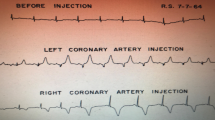

At the end of CAG, IMR was measured in patients with CSX with a thermodilution technique as described previously [9]. Briefly, the aortic pressure transducer was zeroed to air, and after routine preparation and calibration, the pressure wire was introduced in the guide catheter and positioned with the wire sensor at the guide tip for electronic equalization. The pressure wire was advanced to the distal part of the coronary artery (approximately two-thirds of the vessel). After intracoronary injection of 250 mg of isosorbide dinitrate, the following parameters were measured, both at baseline and after hyperemia was induced with intravenous infusion of adenosine at a rate of 140 mg/kg/min: (1) mean aortic pressure, (2) mean distal pressure, and (3) mean transit time. The mean transit time was calculated as the average of three transit time measurements during three separate injections of 3 ml 0.9% saline at room temperature. IMR was then calculated as the mean distal pressure at hyperemia multiplied by the mean transit time at hyperemia. Equally, the calculation of IMR was also performed independently by two experienced operators who were blinded to the clinical grouping.

A total of 23 patients with CSX were enrolled, including 13 patients in the RIPC group, with 17 diseased vessels (nine vessels of eight patients in the UL subgroup and eight vessels of five patients in the LL subgroup), and 15 diseased vessels of 10 patients in the control group (six vessels of four patients in the UL subgroup and nine vessels of six patients in the LL subgroup). The results demonstrated that IMR decreased significantly in the experimental group after RIPC; no significant difference was observed in the control group (P > 0.05) (Fig. 3). Further data analysis demonstrated no significant difference in the decrease of IMR between the UL and LL subgroups of the RIPC group (P = 0.555) (Table 4).